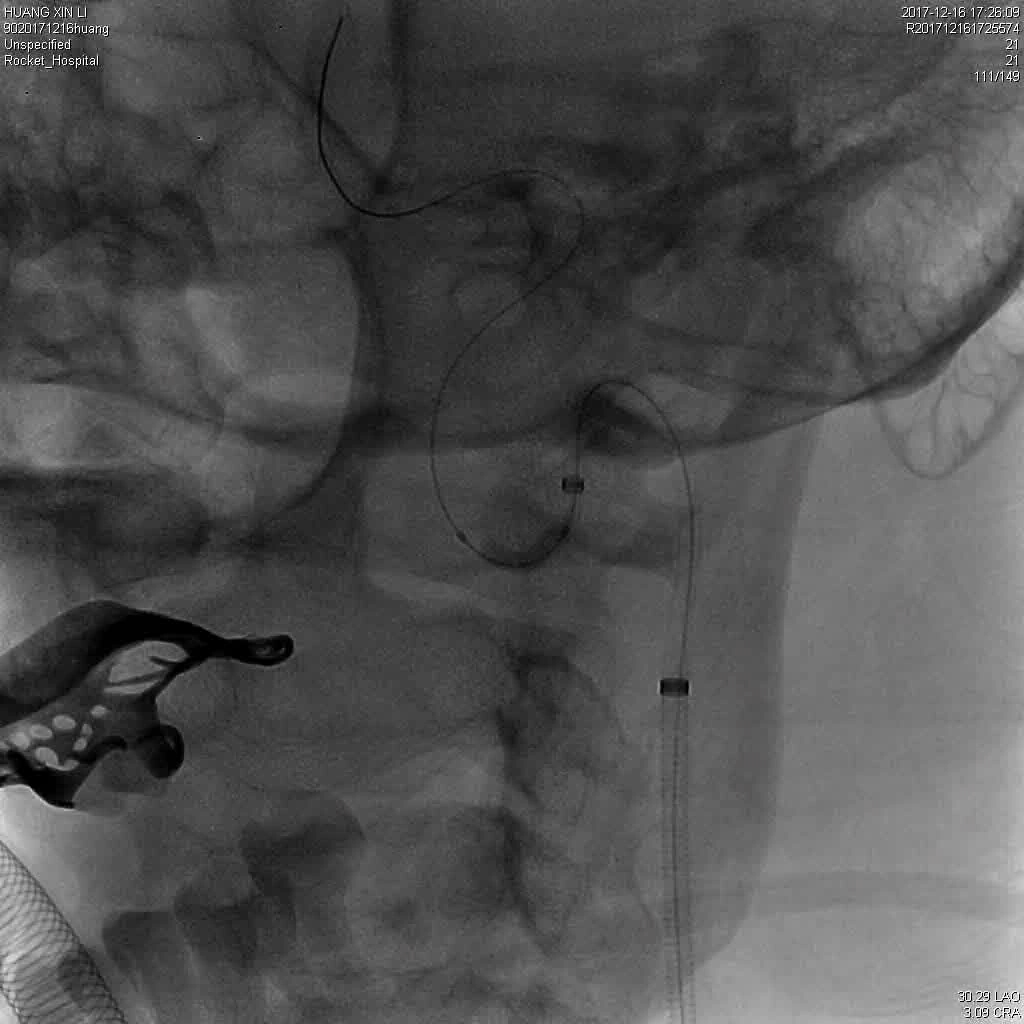

手术过程

中间导管配合在长鞘和小球囊的配合下穿过迂曲夹层的颈内动脉。

微导管微导丝越过MCA闭塞段,置入取栓支架支架。

微导管微导丝穿过夹层段,4.0×20mm球囊再次反复贴附夹层段,促进内膜贴壁。